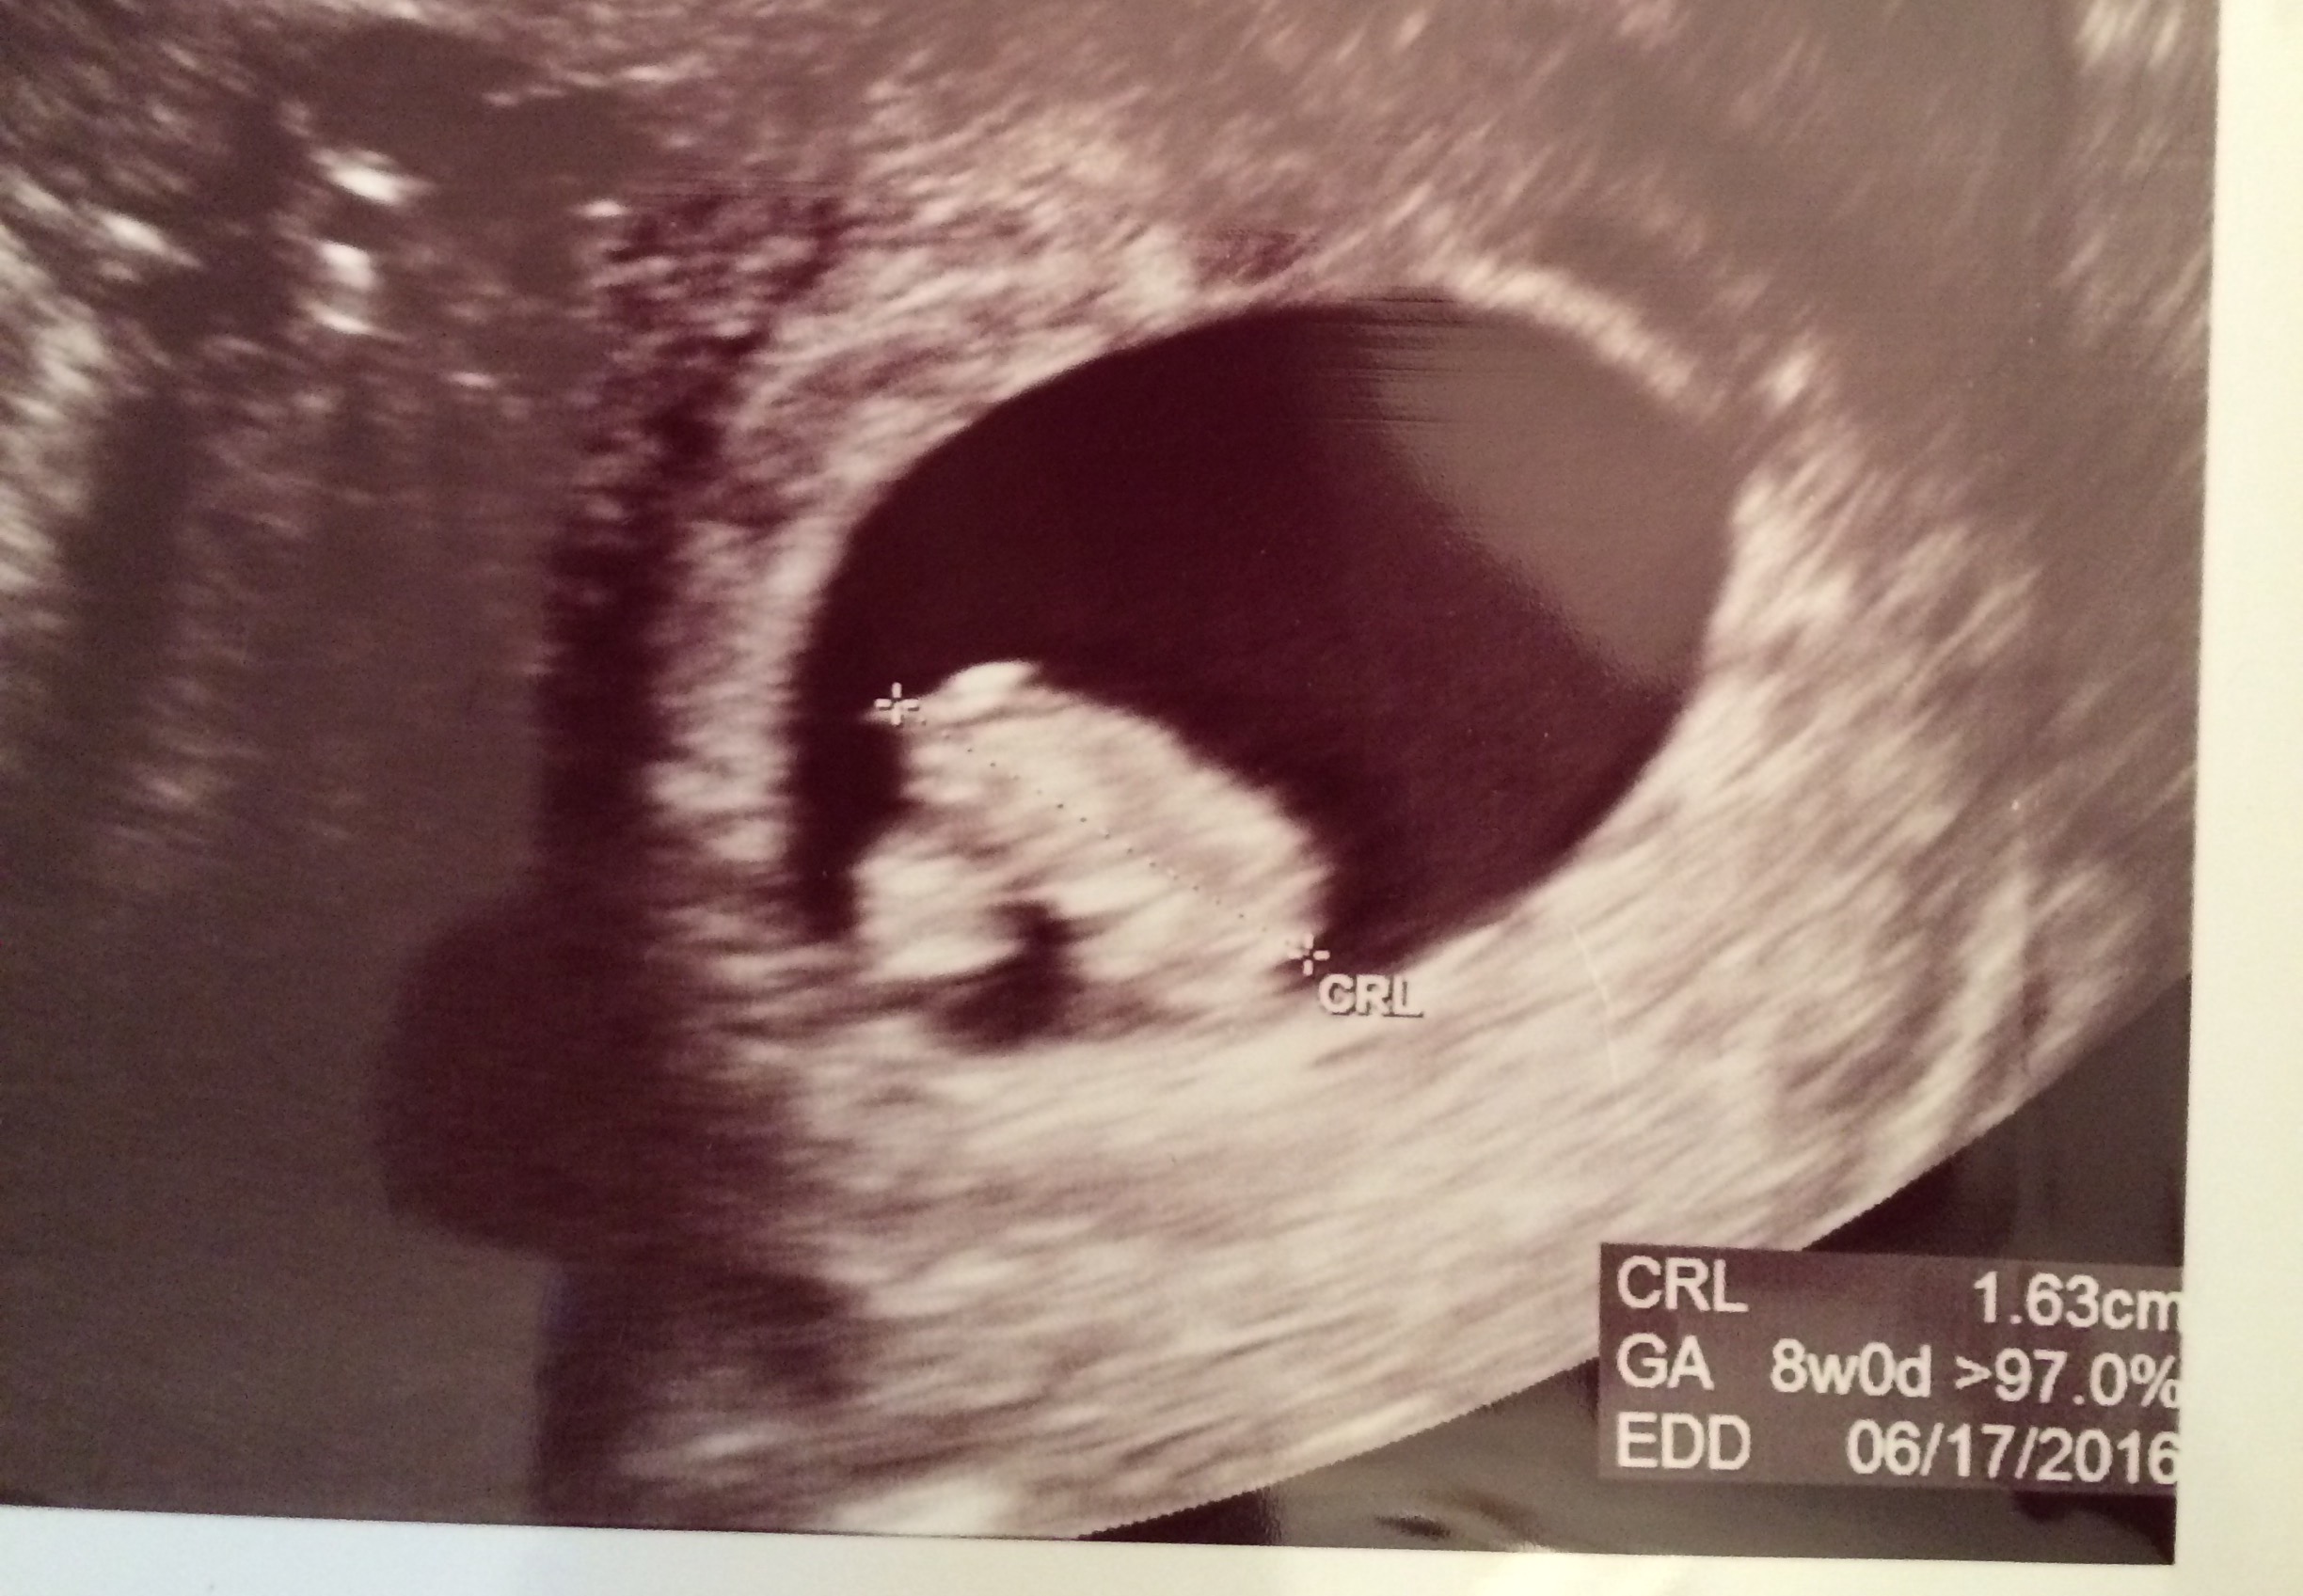

FTM! So excited to see how much my little gummy bear has grown in two weeks! 1st pic is at 6w5d, HR 147, and just a little blob with a flickering heart. 2nd & 3rd pics are at 8w5d, HR 176, and looked so much like a tiny baby with bitty arms and legs. Doc says baby is healthy and quite a dancer, it was moving and waiving all over the place. What a blessed moment to see!